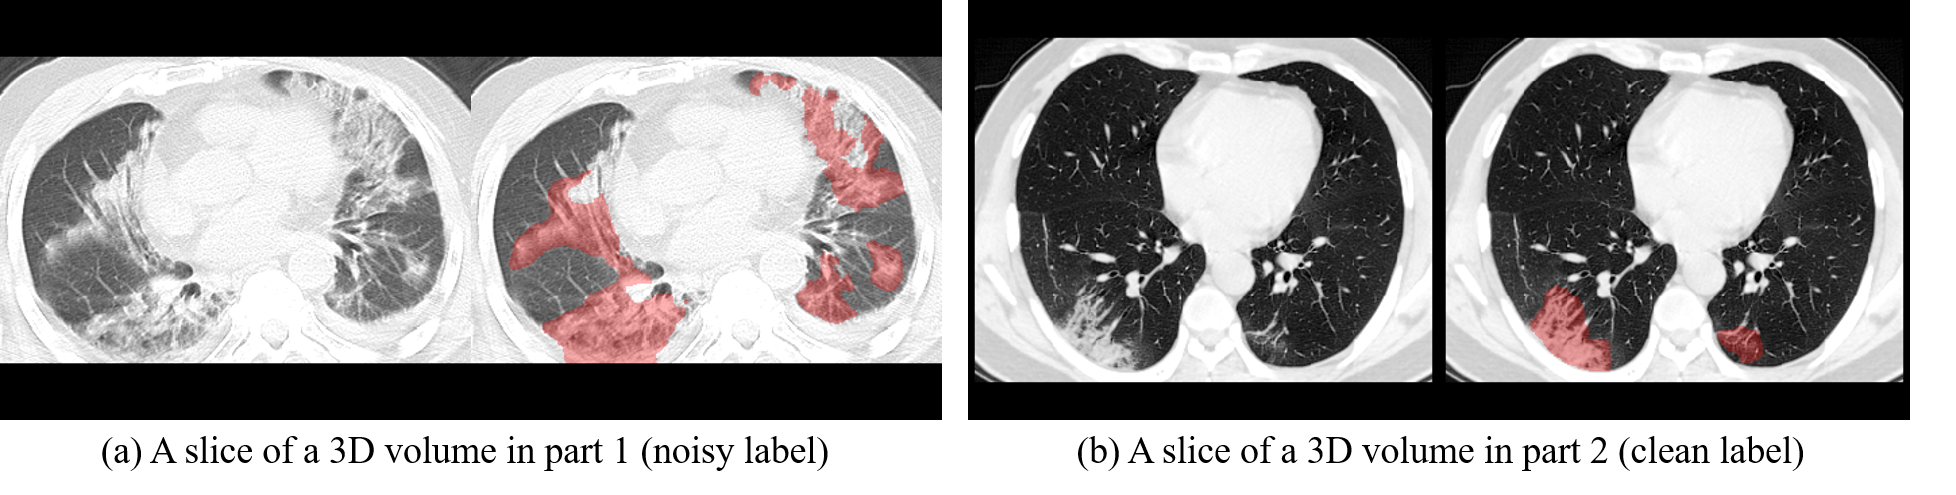

1,UESTC-COVID-19 Dataset [Downlaod]

This dataset contains CT scans (3D volumes) of 120 patients diagnosized with COVID-19. It was constructed for the purpose of pneumonia lesion segmentation. It contains two parts: 1) Part 1 consists of 70 volumes where lesion regions were annotated by non-experts and the lesion labels contain some noise. 2) Part 2 consists of 50 volumes where leions were annotated by experts, and the labels can be seen as clean. References:

Guotai Wang, Xinglong Liu, Chaoping Li, Zhiyong Xu, Jiugen Ruan, Haifeng Zhu, Tao Meng, Kang Li, Ning Huang, Shaoting Zhang. “A Noise-robust Framework for Automatic Segmentation of COVID-19 Pneumonia Lesions from CT Images.”IEEE Transactions on Medical Imaging, 39, no. 8(2020): 2653 - 2663.

Shuojue Yang, Guotai Wang*, Hui Sun, Xiangde Luo, Peng Sun, Kang Li, Qijun Wang, Shaoting Zhang. “Learning COVID-19 Pneumonia Lesion Segmentation from Imperfect Annotations via Divergence-Aware Selective Training”.IEEE Journal of Biomedical and Health Informatics (JBHI), 26, no. 8 (2022): 3673-3684.